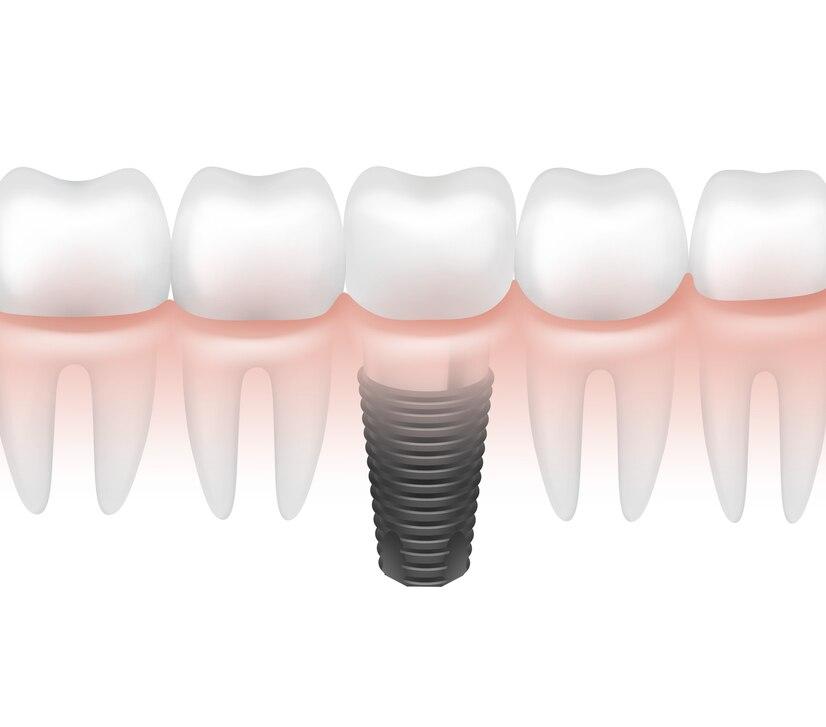

One long-term option for restoring lost teeth is dental implants. They are comprised of a custom-made crown that mimics a natural tooth, an abutment that joins the post to the crown, and a titanium post that is surgically placed into the jawbone. For lost teeth, this restoration offers a robust, long-lasting, and aesthetically pleasing substitute.

- Initial Consultation: A dentist assesses your oral health and determines if you are a good candidate for implants.

- Implant Placement: The titanium post is surgically inserted into the jawbone and allowed to heal over several months.

- Abutment Placement: Once the implant fuses with the bone, an abutment is attached to hold the crown.

- Crown Placement: A custom crown is secured to the abutment, completing the restoration.